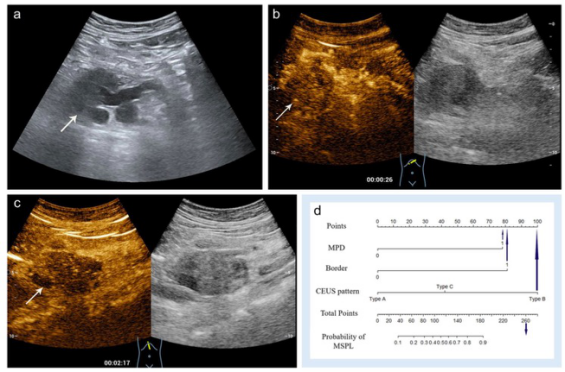

圖 一位60歲的女性,胰頭處有一個直徑為5.3厘米的低回聲實性病變。a 病變顯示邊界不清(箭頭)、主胰管擴張(9毫米)。 b, c 動脈期(b)和靜脈期(c)均顯示腫瘤低強化。病理顯示為分化不良的胰腺導(dǎo)管腺癌

本研究表明,在CEUS上,在AP和VP上表現(xiàn)為低強化、高或等強化或廓清、邊界不清以及MPD擴張是MSPLs的獨立風(fēng)險因素,因此本研究提出的基于這些預(yù)測因素構(gòu)建的列線圖可作為診斷MSPLs的一個有效影像學(xué)工具為臨床提供服務(wù)。